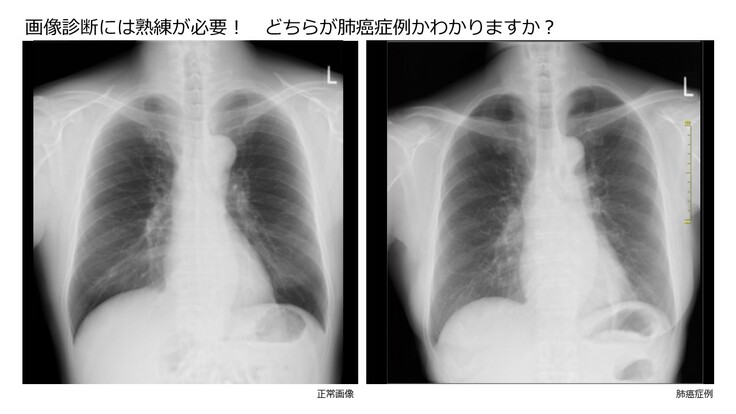

●医師の画像診断精度の現状

このように現代の医療ではX線、超音波、内視鏡などは内科でまず最初に行われる画像診断であり、正しい診断や治療のために不可欠な手段ですが、正確な診断には高度な専門知識と熟練が必要です。しかし正確な画像診断を行うことができる「専門医」は医師の10名にひとりもいないために、医療機関によって画像診断の精度には「ばらつき」が大きいのが現状です。

「専門医」になるためには医師免許取得後、10年近い臨床経験を経て試験に合格する必要があります。日本では画像診断の「専門医」に限らず、「専門医」を育成する体制が十分に整っていないために、先進国の中でも「専門医」が非常に少ないという問題があります。その結果、現在のコロナ禍においても「新型コロナウイルス」という新しい感染症に対応できる「専門医」が少なく、医療崩壊を起こしやすいという構造的な課題を抱えています。

画像診断についても「専門医」不足により平常時でも多くの研修医が臨床での十分な指導を受けることができないまま、臨床現場に配属されるケースが生じます。このように医師を育成する環境は必ずしも望ましいものではなく、平常時でも癌の見落としなどによる死亡例が散見されています。すなわち医師も患者も見落としによる治療の遅れや医療過誤のリスクに常にさらされていることになります(下図)。